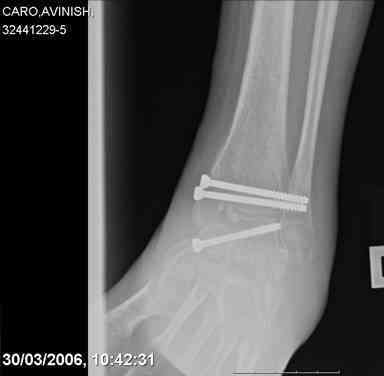

Re: Осколчатый перелом таранной кости

ya by popytalsya sobrat talus anatomichno,seichas pozdno operirovat iz za oteka,po etomy distrakziya apparatom budet optmalna.Posyalu vam podobyai moi sluchai.

14 years old girl

Fall from height ( 3rd floor)